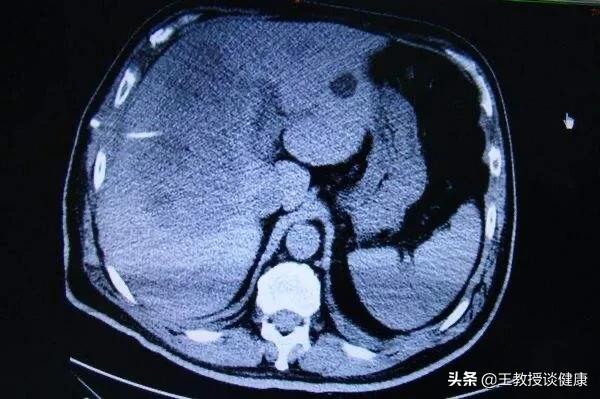

全身应用有效抗生素一周的影像